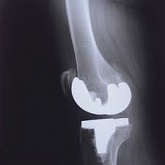

Еndoprosthesis of knee joint

In the late stages of arthrosis of the knee joint, accompanied by a pronounced restriction of the volume of movements, constant intense pain, deformity of the limb, the only way to recover is to replace the affected joint with an artificial joint - arthroplasty.

This method allows you to return the correct form of the limb, the full volume of movements in the joint, relieve the constant pain and crunch during movements and, as a result, significantly improve the patient's quality of life.

Below are presented X-ray photographs and photographs, illustrating the amount of motion in the affected joint before and after surgery.